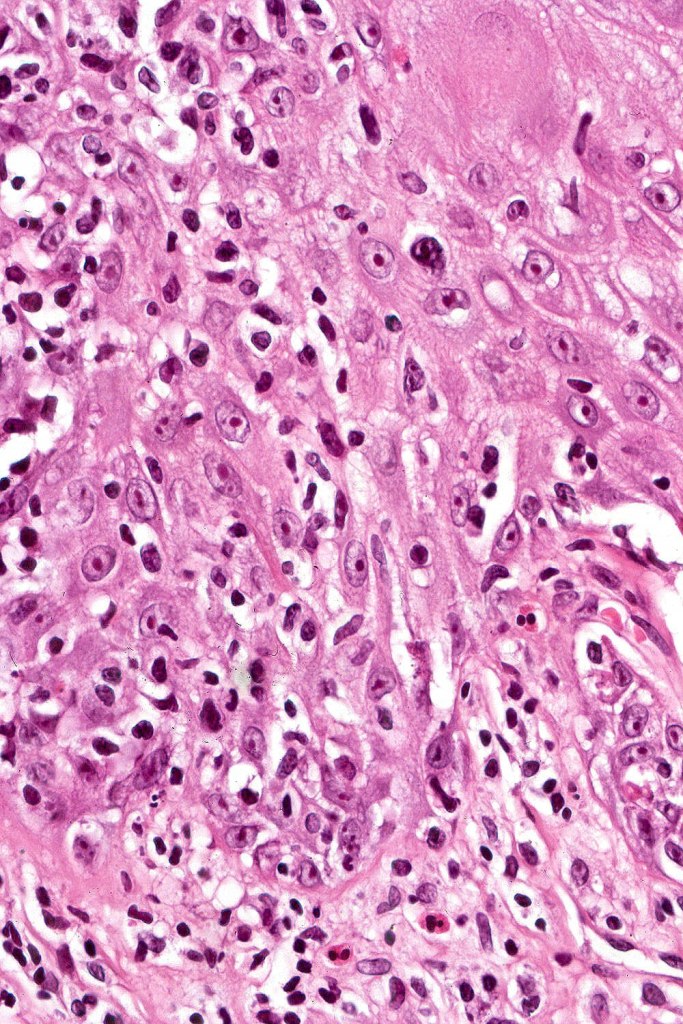

Histological features

The histological hallmark of mycosis fungoides is the presence of large atypical lymphocytes with a convoluted/cerebriform nuclear border (Sézary cells). These may be found at the epidermal-dermal jnuction and as collections within the epidermis (Pautrier microabscess). These are most easily found in plaque stage disease. The epidermal component can be subtle in patch stage disease and is often lost in tumor stage dsease. The classification into patch, plaque & tumor stage disease is less helpful histologically as the features merge from one to the other. It is all a matter of degree.

Tumor Stage Disease

•Epidermotropism is often minimal or absent

•Dense, broad diffuse or nodular, dermal infiltrate often extending into the subcutaneous fat

•Abundant Sézary cells. Frequently accompanied by very pleomorphic forms

•Mitoses often abundant, frequently abnormal

•CD30 expression correlates with transformation (cells X4 size of small lymphocytes comprising 25% or more of the infiltrate or the presence of a distinct large nodule)